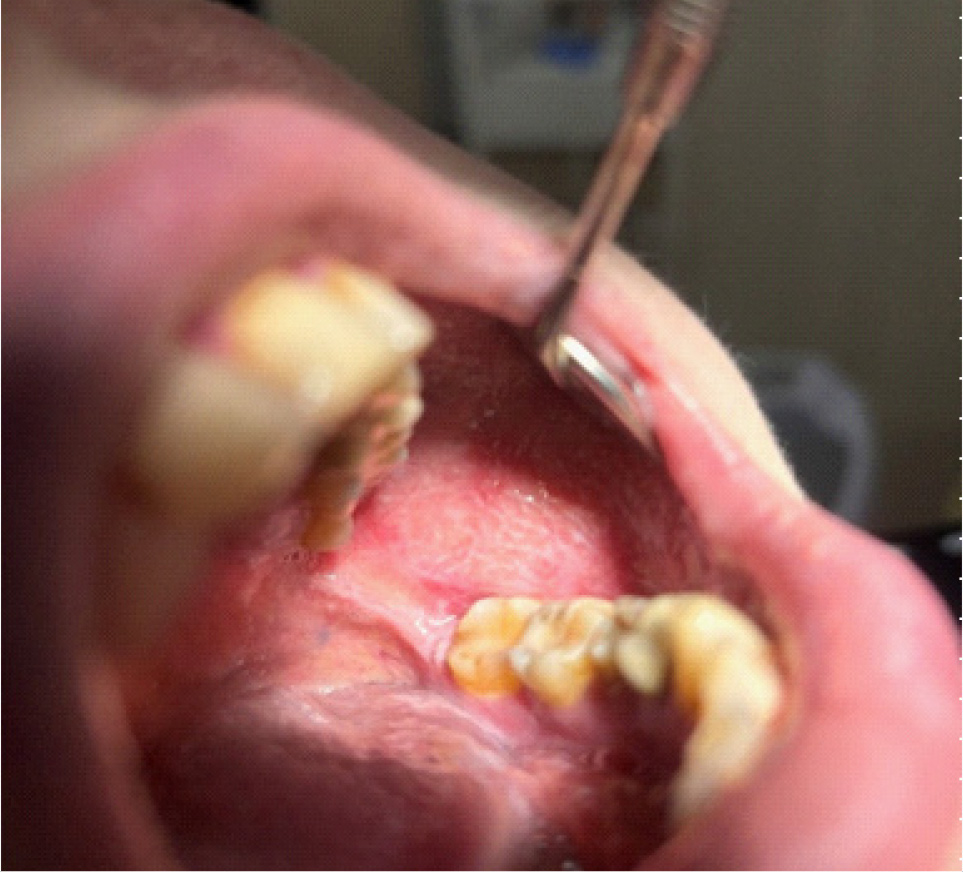

Объективные данные обследования. Общее состояние на момент осмотра удовлетворительное. Конфигурация лица изменена за счет послеоперационных явлений. Определяется послеоперационная рана с гнойно-воспалительными явлениями. Определяются явления лучевого остеонекроза нижней челюсти справа (рис. 9–11). Открывание рта ограничено, умеренно болезненное. Лечение на амбулаторном этапе заключалось в активной санации гнойно-некротических проявлений в раневой поверхности, активное орошение антисептическими растворами, протеолитическими ферментами. Активная антибактериальная, противовоспалительная, симптоматическая терапия.

Рис. 9. Клинические проявления лучевого остеонекроза нижней челюсти справа

Рис. 10. Клинические проявления лучевого остеонекроза нижней челюсти справа на этапе лечения

Рис. 11. Клинические проявления лучевого остеонекроза нижней челюсти с развитием патологического перелома нижней челюсти справа

На 10-е сутки от начала лечения пациента на амбулаторном этапе на фоне снижения гнойно-некротических явлений в ране пациент обратился к врачу – стоматологу-хирургу с жалобами на патологическую подвижность нижней челюсти справа в проекции очага лучевого остеонекроза. При осмотре диагностирован патологический перелом нижней челюсти справа, пациент госпитализирован в отделение челюстно-лицевой хирургии для дальнейшего лечения.